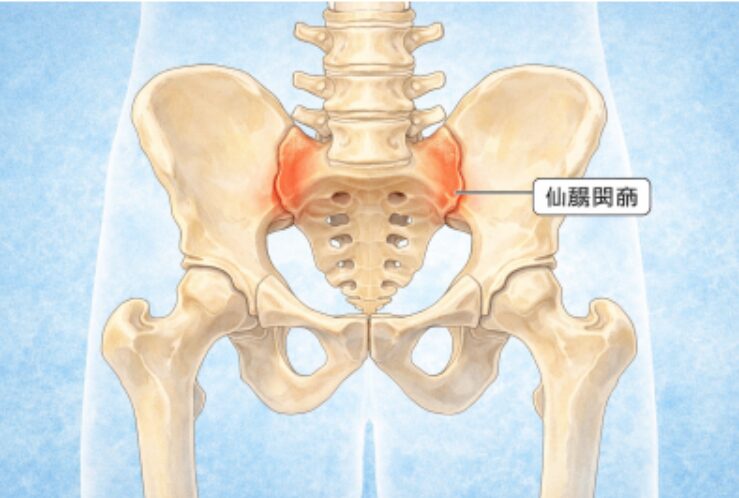

今回の症状の原因は、仙腸関節の硬さが問題でした。

仙腸関節は、

骨盤を構成するのに重要な関節です。

動きはとても小さく、

「ほとんど動かない関節」と言われることもありますが、

実はこのわずかな動きが、体全体のバランスを保つうえでとても重要です。

例えるなら、

家の基礎と柱をつなぐ“金具のような存在。

派手には動かないけれど、

ズレると家全体が傾いてしまいます。

あぐらをかくと、

股関節が外に開き、膝が横に落ちます。

このとき多くの人は、

・骨盤が後ろに倒れる

・左右どちらかに体重をかける

・背中が丸くなる

という姿勢になりやすくなります。

この時の仙腸関節の状態を例えると、

少し歪んだままドアを閉め、鍵をかけてしまった状態

です。

閉まってはいるけれど、

・開け閉めがスムーズじゃない

・きしむ

・他の部分に無理がかかる

この状態で立ち上がったり歩いたりすると、

腰・股関節・膝関節が代わりに頑張ることになります。

その結果、今回股関節の痛みが出現してしまったと考えられます。